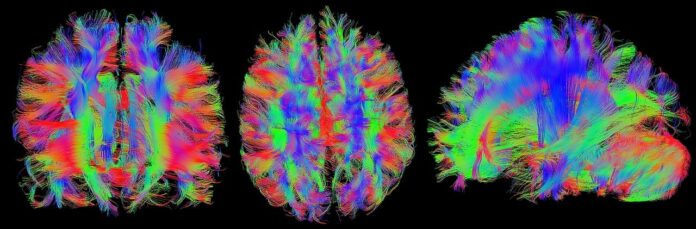

El equipo de científicos, liderado por Harald Sontheimer y Lata Chaunsali, buscaba desentrañar por qué el alzhéimer afecta de forma tan selectiva la memoria afectiva y social. Su investigación se centró en las redes perineuronales (RPN), unas estructuras que rodean y sostienen a determinadas neuronas, y que desempeñan un papel esencial en la comunicación entre células nerviosas, la formación de recuerdos y la estabilidad de las conexiones neuronales. Lo que encontraron fue una clave decisiva: cuando estas redes se deterioran, la capacidad del cerebro para reconocer rostros y vínculos emocionales comienza a debilitarse.

Para comprobar su hipótesis, realizaron experimentos con ratones que replicaron de forma sorprendente el patrón observado en los seres humanos. Los animales con RPN deterioradas dejaron de reconocer a otros ratones, pero siguieron recordando objetos de su entorno sin dificultad. Esta separación tan clara entre memoria social y memoria de objetos permitió a los investigadores confirmar que la pérdida de la memoria afectiva no es un proceso generalizado, sino un fenómeno selectivo asociado directamente al daño en estas estructuras neuronales. El paralelismo con lo que ocurre en pacientes humanos resultó ser profundamente revelador.

Pero el estudio no se limitó a identificar el mecanismo, sino que también exploró soluciones potenciales. Los científicos probaron inhibidores de las metaloproteinasas de matriz (MMP), una familia de fármacos que ya se utiliza para tratar ciertos tipos de cáncer y artritis. Los resultados fueron especialmente prometedores: al aplicar estos medicamentos, lograron evitar la degradación de las RPN y preservar la memoria social en los ratones. Esto significa que la desintegración de las estructuras que protegen a las neuronas puede frenarse con fármacos existentes, lo que abre una posible vía terapéutica mucho más cercana de lo que se pensaba.

La relevancia de este avance se vuelve aún más evidente si se considera que, solo en España, cerca de 800.000 personas viven actualmente con alzhéimer, según datos recientes de la Sociedad Española de Neurología. Comprender por qué los pacientes pierden los recuerdos más significativos y encontrar herramientas para preservarlos constituye uno de los mayores retos de la neurociencia moderna. Esta investigación aporta una pieza fundamental del rompecabezas y abre un horizonte esperanzador para el futuro.